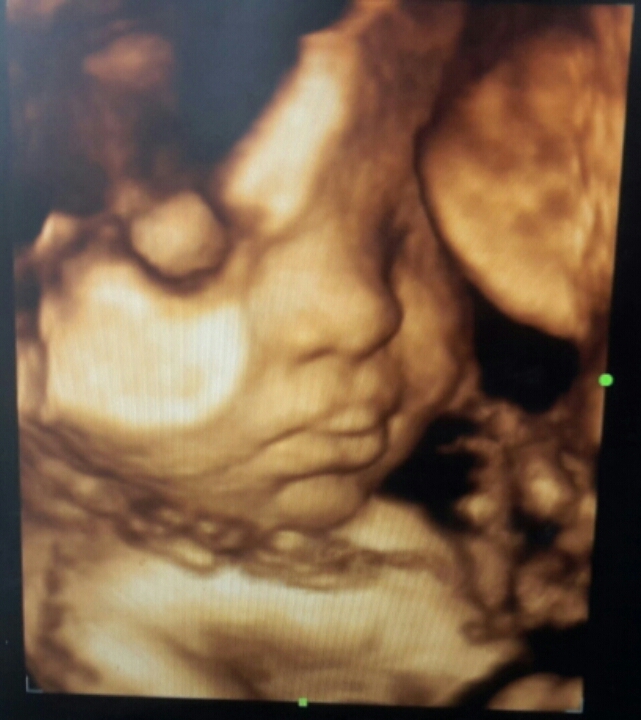

Fateh di alam rahim

40 minggu a.k.a 10 bulan